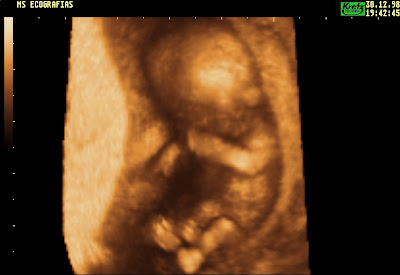

ECOGRAFIA 3D ÀS 10 SEMANAS DE GESTAÇÃO

Uma das questões mais discutidas no debate do referendo do aborto é a questão da vida de um feto com 10 semanas.

Será um feto com 10 semanas uma vida humana?

Sim, é! Sem dúvida que é!

Um feto com 10 semanas é um ser humano!

Um feto com 10 semanas possui o seu próprio código genético, que torna este novo ser diferente de todos os outros seres humanos que viveram no passado, vivem no presente e viverão no futuro!

Mas como uma imagem vale mais do que mil palavras, sugiro a todos (aos que ainda têm dúvidas e aos que já não têm) que visitem o site http://www.medicosporissonao.com/

Trata-se do site do movimento "Somos médicos, por isso Não", onde se encontram inúmeros videos sobre a vida intra-uterina, ecografias 2D e 3D às 10 semanas e muitas fotografias que não deixam qualquer dúvida:

a vida humana começa na concepção!

um feto com 10 semanas é uma vida humana!

Às dez semanas está completo um quarto da vida intra-uterina, iniciada na concepção com o zigoto que resultou da união do espermatozóide e do óvulo. O então denominado feto, com um código genético único, já possui todos os órgãos e sistemas corporais, que se encontram em crescimento e diferenciação aceleradas. O sistema nervoso central, que se vai desenvolver durante toda a vida, surgiu às três semanas, já apresenta os hemisférios com córtex (substância cinzenta) e tem actividade cerebral, que se regista em traçados electroencefalográficos. Verificam-se movimentos espontâneos dos braços e pernas, possuindo músculos e dedos, com unhas e impressões digitais. Os olhos têm pálpebras, íris e córnea, a boca tem língua e engole líquido amniótico. Surgiram os primeiros folículos capilares, de onde em breve nascerá cabelo. Os rins já produzem urina. Estão diferenciados os órgãos sexuais masculinos e femininos. O coração está formado, assemelha-se ao do adulto e cumpre a sua função circulatória, que assegura o crescimento do feto, com uma frequência cardíaca média de cerca de 175 pulsações por minuto.

Às dez semanas existe um ser humano complexo e em desenvolvimento até ao nascimento.